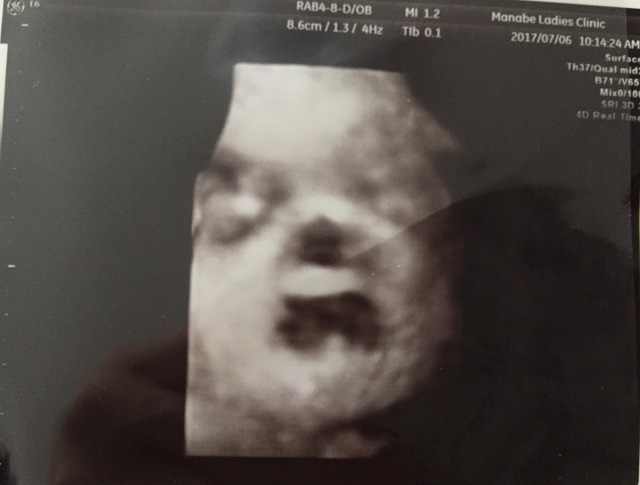

31週1日(31w1d・女の子)|Fatima さん(26歳)

エコー写真撮影時のエピソード:

私の通っていたクリニックでは、20週以降、4Dエコーを撮ってもらえました。毎回うずくまってガッツポーズだったため、性別が確定したのも30週を超えてから。これは、ようやく顔が撮れた時の奇跡の一枚です。鼻と口元が旦那そっくり!